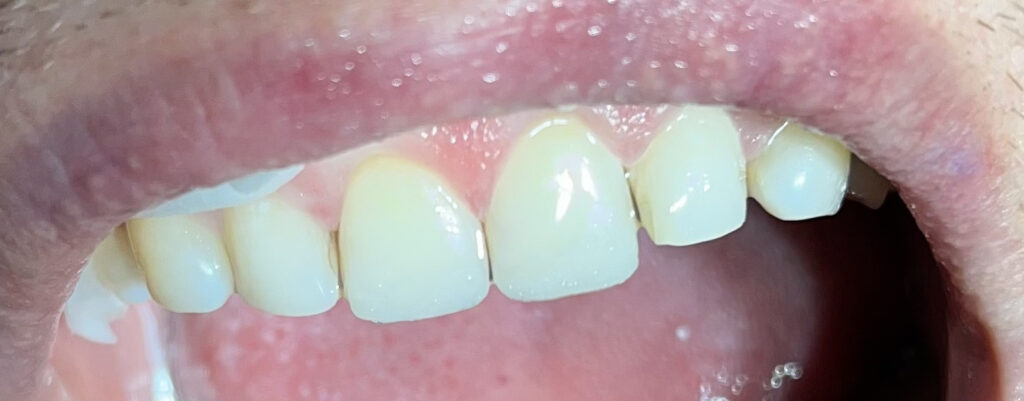

Każdy uśmiech ma swoją historię – my pomagamy ją opowiedzieć na nowo. Dzięki indywidualnie dobranym planom leczenia przywracamy pacjentom nie tylko piękny wygląd zębów, ale również komfort i funkcjonalność w codziennym życiu. Poniżej przedstawiamy wybrane przypadki metamorfoz, które pokazują, jak zaawansowana protetyka, nowoczesne techniki odbudowy oraz precyzyjne leczenie endodontyczne potrafią całkowicie odmienić uśmiech.